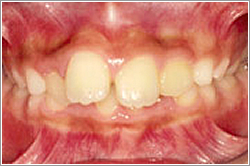

上顎前突ともいいます。

上の前歯が前方に出ていて、前歯でそばなどが噛み切れない状態。笑った時に上の前歯が目立って見える歯並びです。

口を閉じても前歯が見えてしまうこともあります。

上の前歯がでております。